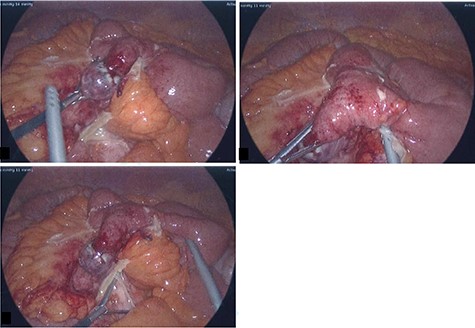

He was commenced on intravenous antibiotics and underwent an initial laparoscopy where an inflamed MD with local perforation was found with significant surrounding inflammation, a normal appendix was confirmed (Fig. 2). The decision was made to convert to a mini-laparotomy given the need for a small bowel resection with subsequent stapled side to side anastomosis. On macroscopic examination of specimen in the operating theater, a corn kernel was found obstructing the lumen of the diverticulum.

Intra-operative photos: acutely inflamed MD with a wide base and gangrenous tip, associated with significant surrounding inflammation.